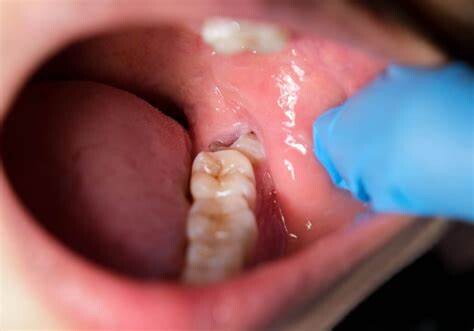

Wisdom teeth promotes Gum Disease

It is a challenging task to clean the area in which the third molars have erupted. Therefore they are at a greater risk of acquiring the periodontal problems. The gum diseases are usually caused by bacteria, and when a tooth can’t be precisely cleaned on a regular basis, the dental plaque gets accumulated around the tooth, which may lead to further complications.

Tooth Decay

The fully impacted or the partially impacted wisdom teeth are at greater risk of tooth decay, than other teeth. This usually happens, because of the location of the wisdom tooth, especially towards the back of the mouth, which is hard to clean. Moreover, since it lies at the back of the mouth, there are chances of food getting easily trapped between the gums and the tooth, promoting the growth of bacteria.

You can’t prevent the occurrence of an impacted wisdom tooth, but with a regular dental check-up, your dentist will help you monitor the emergence of the wisdom tooth, with the help of dental X-rays and advanced methodologies, which might indicate the need of wisdom teeth removal.